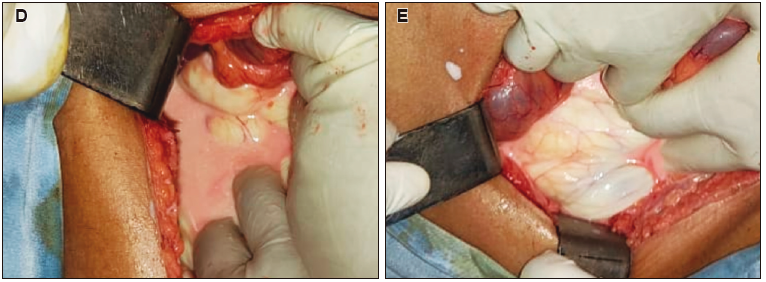

Se decide realizar una laparotomía exploradora, con hallazgo de líquido quiloso en la cavidad abdominal (Figura D) y compromiso retroperitoneal (Figura E), sin identificar el sitio de la fuga linfática. Se lava profusamente con solución fisiológica y se colocan drenajes al retroperitoneo y al espacio de Douglas.

Figura. D) Laparotomía exploradora. Hallazgo de líquido quiloso en la cavidad peritoneal. E) Laparotomía exploradora. A través de la fascia de Toldt se observa líquido libre en el retroperitoneo